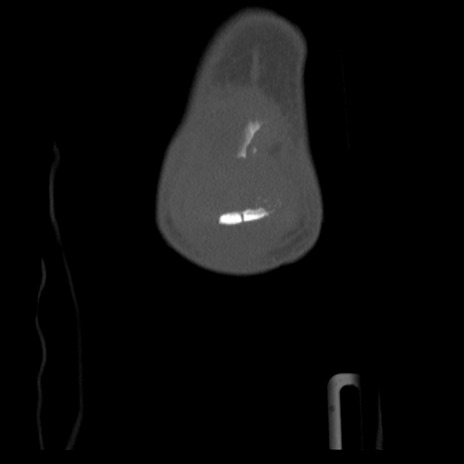

右膝関節CT

横断像